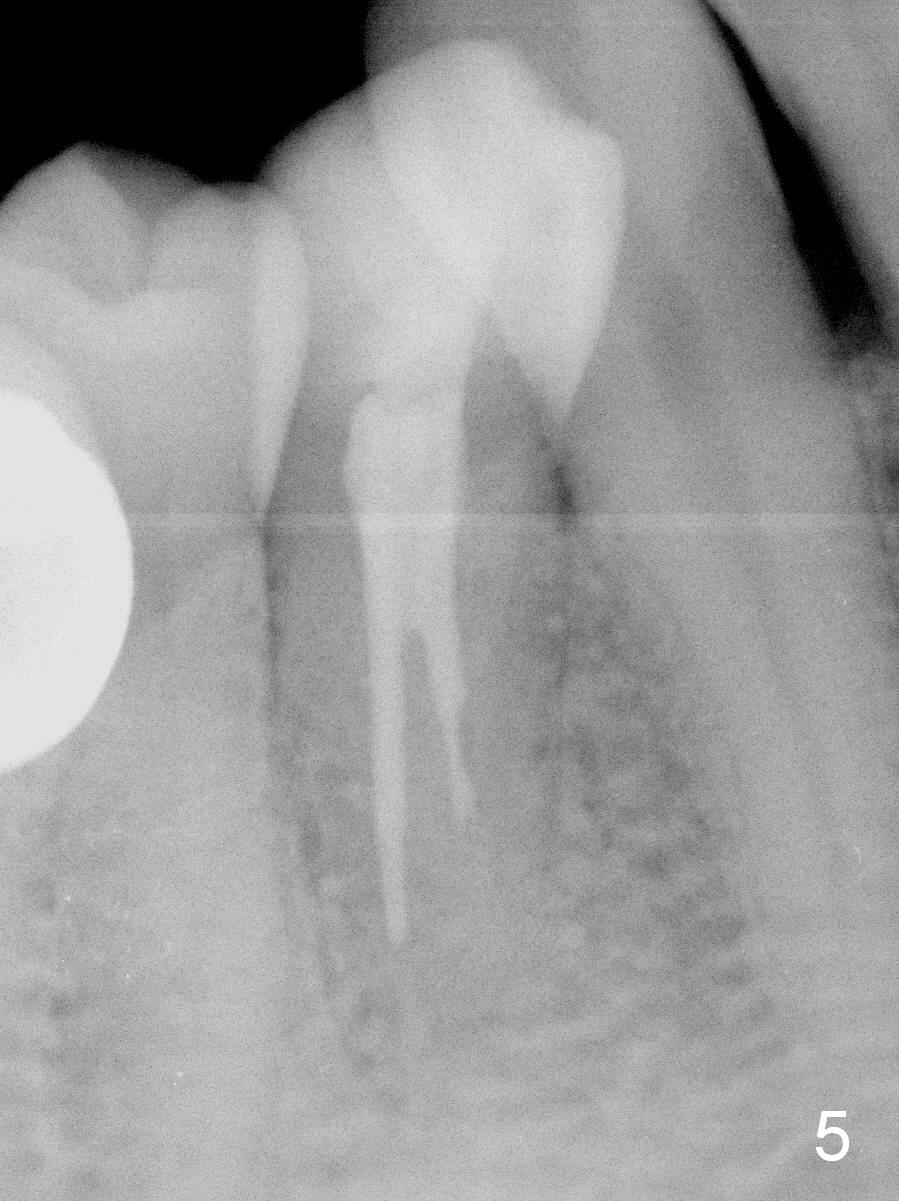

Further exploration finds a lingual canal (Fig.2), which is debrided until 30 hand file. When the canals are being filled with gutta percha and paste, the lingual canal is not filled (Fig.2). After removal of buccal gutta percha, the lingual canal is enlarged with 30/.04 rotary file and filled (Fig.4). The lingual canal is laterally condensed; composite build up is finished (Fig.5).

In fact CBCT has ben taken for #14 RCT and is reviewed prior to this case. If CT were reviewed, finding the extra canal would be easier (Fig.6 coronal section). It appears that the apical canals are blocked (Fig.7). The canal is split at the middle of the root, as shown in Fig.8,8' (axial upper section, as shown by the upper dashed line in Fig.6) and in Fig.9,9' (axial lower section, as shown by the lower dashed line in Fig.6). The buccal canal should not have been debrided with 40/.04 rotary file (30/.04 would have been better). In all, the tooth has two fused roots (Fig.3,9,9').